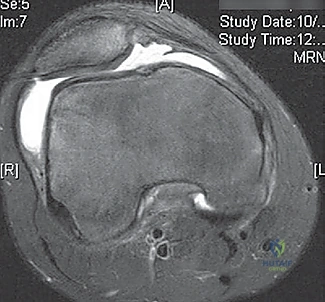

- MRI Scan: Highly recommended for all patients with a large traumatic effusion due to the high rate of occult articular or osteoarticular injury.

* Osteochondral Lesions: Crucial for determining size, location, and potential for repair versus removal.

* Bone Bruise Pattern: Confirms patellar dislocation (medial patella and lateral femoral condyle).

* Anatomical Risk Factors: Assesses patella alta, trochlear dysplasia, tibial tubercle-trochlear groove (TT-TG) distance.

* Bone Bruises: MRI often reveals increased signal on the medial patella and the midportion of the lateral femoral condyle. This distinct pattern helps differentiate it from ACL tears.